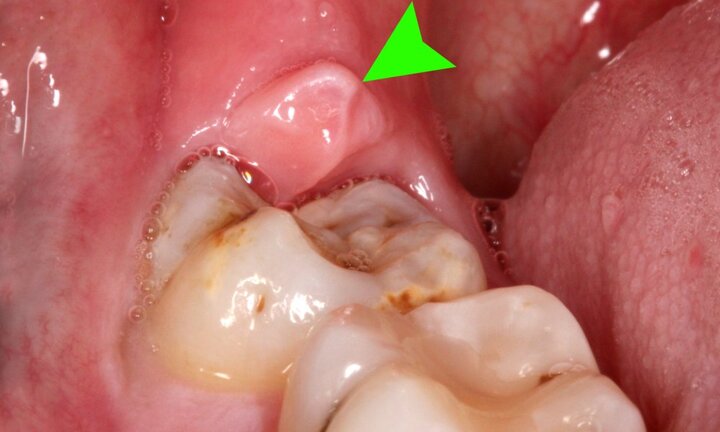

Răng số 8 là răng gì?

Mới đây, một nữ bệnh nhân ở Quảng Ninh qua đời nghi do sốc phản vệ trong khi nhổ răng số 8 xôn xao dư luận, vậy răng số 8 là răng gì?